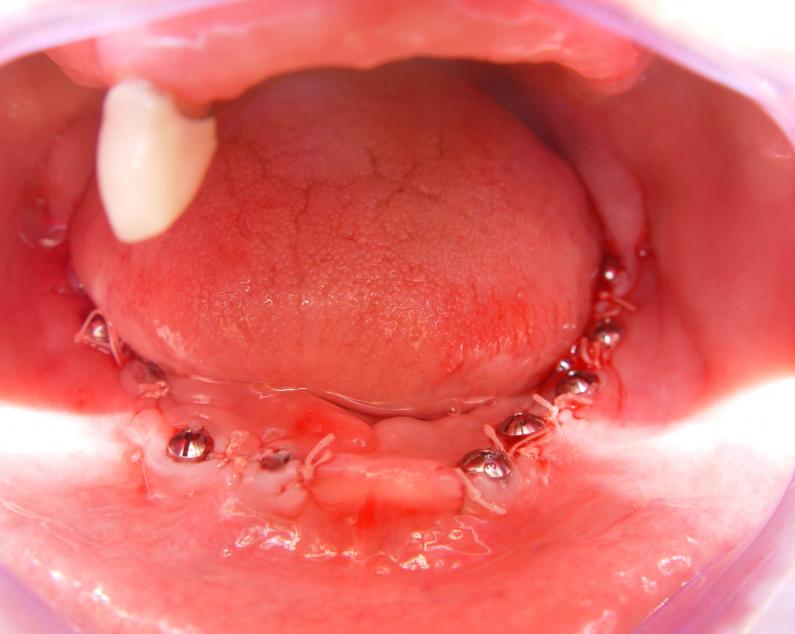

Фото →Установка 10 имплантантов на беззубую челюсть с помощью компьютерной программы: Имплантанты установлены